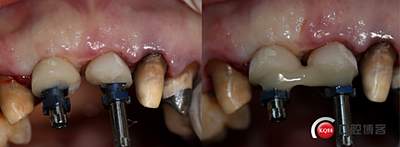

制作個(gè)性化轉(zhuǎn)移桿,對(duì)齦緣壓迫塑形。

取模。

全瓷冠制作完成,齦乳頭預(yù)留空間不足,修整三角間隙。

戴牙。